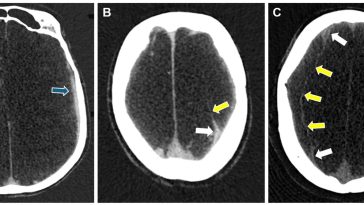

Revolutionizing Chronic Subdural Hematoma Care Through Advanced Diagnostics and Treatment

Chronic Subdural Hematoma: A Shifting Landscape in Neurosurgical Care The management of chronic subdural hematoma (CSDH) has been a topic of heated discussion in the healthcare community for many years. With an annual incidence that ranges from 1.7 to 20.6 per 100,000 people—and climbing due to an aging global population and increasing use of anticoagulant […] More